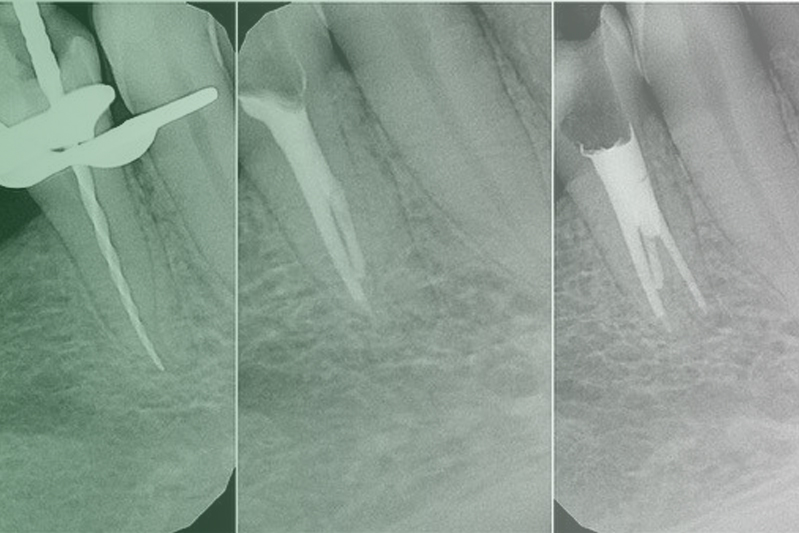

Клинический случай. Эндодонтия